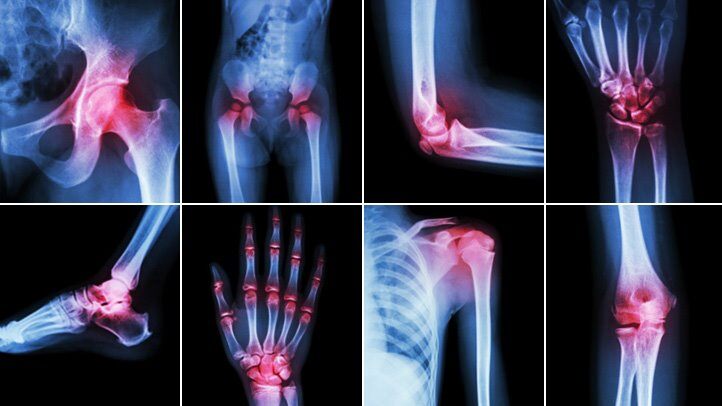

Свикнали сме да възприемаме болките в ставите като следствие от прекомерно физическо натоварване, травми или стареенето на организма. Оказва се обаче, че редица болести са пряко или косвено свързани с костната система и нейното състояние.

Хората с анемия страдат от недостиг на червени кръвни телца или имат дефицит на червени кръвни клетки. Тъй като функцията им е да пренасят кислород в организма, поддържането на определено количество е много важно. Появата на кислороден дефицит създава проблеми, които включват ставна болка и подуване, симптоми подобни на артрит. Той може и да се появи при кръвни клетки, които по някаква причина не произвеждат хемоглобин. Ставите на ръцете и краката започват да се подуват и местата са болезнени при допир.

Сърдечните заболявания са в пряка зависимост от ставното състояние. Оказа се, че влошаването на единия орган води до аналогичен проблем с другия. В действителност тази свързаност засяга 57% от възрастните със сърдечни заболявания. А в случая на пациенти с ревматоиден артрит, честотата е много по-висока. Могат да се появят и симптоми на диабет или високо кръвно налягане.

Това е може би най-пряко свързаната болест със ставите, но тук ще поговорим за нейната поява следствие на прекомерно хранене и липса на движение. Една от причините за това може да се окаже и раждането, но като цяло ставните проблеми могат да провокират много по-тревожни за здравето състояния.

Това е заболяване на опорно-двигателната система и представлява формиране на ново костно образование върху съществуваща кост. Характерно е за по-възрастните и е по-често срещано при хора, които се занимават с физическа работа. Свикнали сме да ги свързваме с болки и схващане във врата, но ставите са основна причина за появата им. Новата костна маса може да притисне нерви, кръвоносни съдове и да доведе до обездвижване и деформация.

Въпреки, че погрешно се смята, че е само факт от миналото, тази форма на артрита е причинена от натрупването на кристали на пикочната киселина в ставите. Обикновено областта е големият пръст на крака, но усещането е много болезнено, ставата се подува и зачервява.

Тази по-малко позната болест може да се появи след възпаления в белия, черния дроб или далак. Цироза или туберкулоза могат да инфектират от своя страна ставните връзки, капсули и сухожилията.